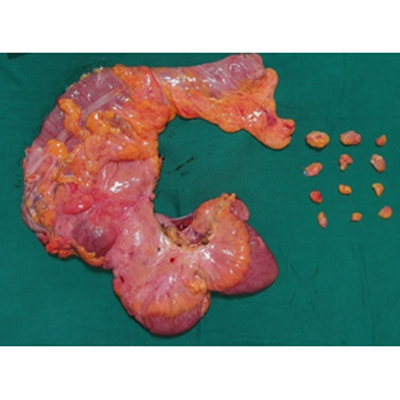

SURGERY FOR COLON CANCER

LAPAROSCOPIC SURGERY FOR PANCREATIC TUMOUR